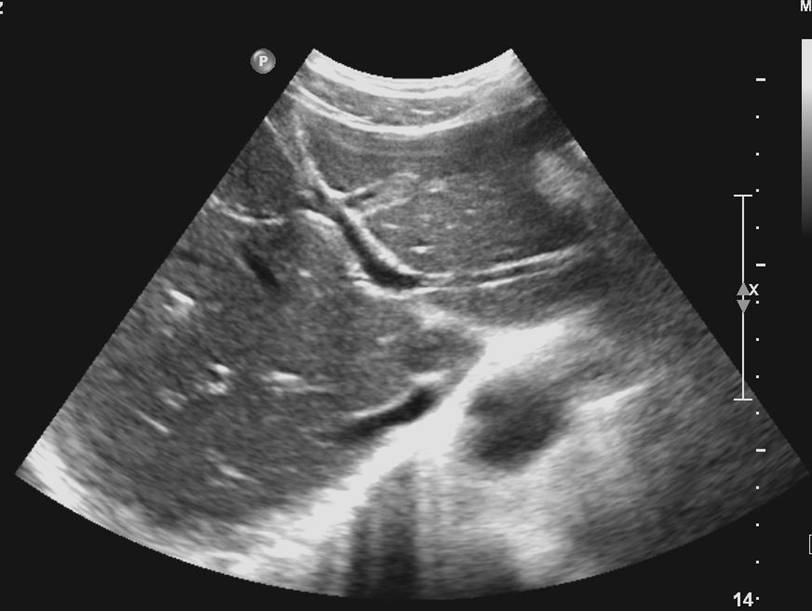

(一)肝静脉

肝静脉分三支即肝左静脉、肝中静脉和肝右静脉,三大肝静脉汇入下腔静脉位于膈肌下方约1cm处,称第二肝门。

分为主干型和分散型:

肝左静脉多为分散型,其主支位于左叶间裂内并进入左外叶上段和下段之间。

肝中静脉主干型多,一般主支大部分位于肝中裂内。

肝左静脉和肝中静脉可先合成短干,然后汇入下腔静脉。

肝右静脉多呈主干型,主干大部分位于右肝叶间裂中,单独汇入下腔静脉。